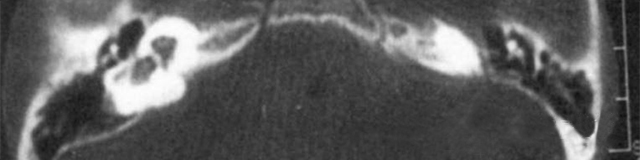

屬常染色體顯性遺傳,是最嚴(yán)重的內(nèi)耳畸形,內(nèi)耳可完全未發(fā)育,可伴有其它器官的畸形和智力障礙。

主要依靠顳骨高分辨CT和內(nèi)耳MRI。

雙側(cè)內(nèi)耳畸形:左側(cè)無內(nèi)耳迷路及內(nèi)耳道機(jī)構(gòu),為米歇爾畸形;右側(cè)空耳蝸及前庭擴(kuò)大,為先天性耳蝸畸形